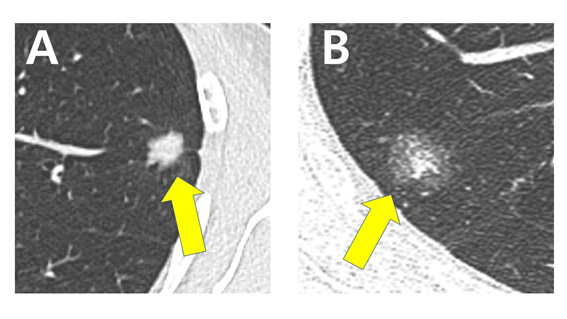

CT 영상에서 폐의 일부분이 불투명한 유리처럼 뿌옇게 보이는 ‘간유리 음영(ground glass opacity)’을 포함한 종양을 가진 환자들에게서는 크기와 상관없이 약 2%의 확률로 수술 검체에서 ‘숨어있는 임파선 전이’가 확인됐다. (1cm 이하 2.27%, 1.0~1.5cm 2.19%, 1.5~2.0cm, 2.18%)

하지만, 결절 전체가 불투명해 ‘순수 고형’ 형태로 보이는 종양을 가진 환자들은 그 크기가 클수록 수술 후 임파선 전이가 확인되는 비율이 높았다. 1㎝ 이하에서 2.46%이던 확률이 1.0~1.5㎝에서는 12.46%, 1.5~2.0㎝에서는 21.31%까지 높아지는 것이 확인됐다.